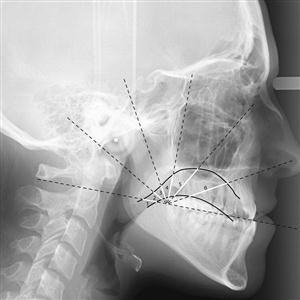

DIGITAL CEPHALOGRAM

Digital Cephalogram = Digital Lateral X.Ray of Skull with Jaw / Mandible for treatment of uneven and protruded / mal-aligned teeth mainly prescribed by orthodontists. Usually required for young patients.